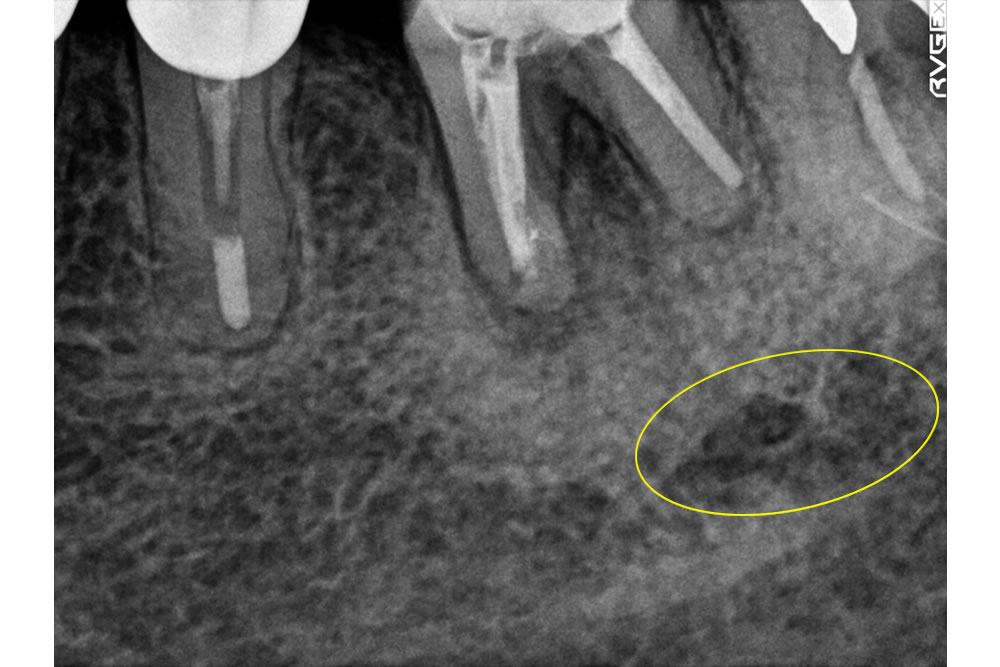

こちらの患者さまは、以前より左下の奥歯にできものが生じ、自然に消えることを繰り返しているとの主訴で来院されました。

レントゲンの写真上でも歯の根の先に膿の貯留が疑われる黒い影があります。

患者さま自身も噛んだ際に違和感があるため、根管治療(歯の根の治療)を行うことになりました。